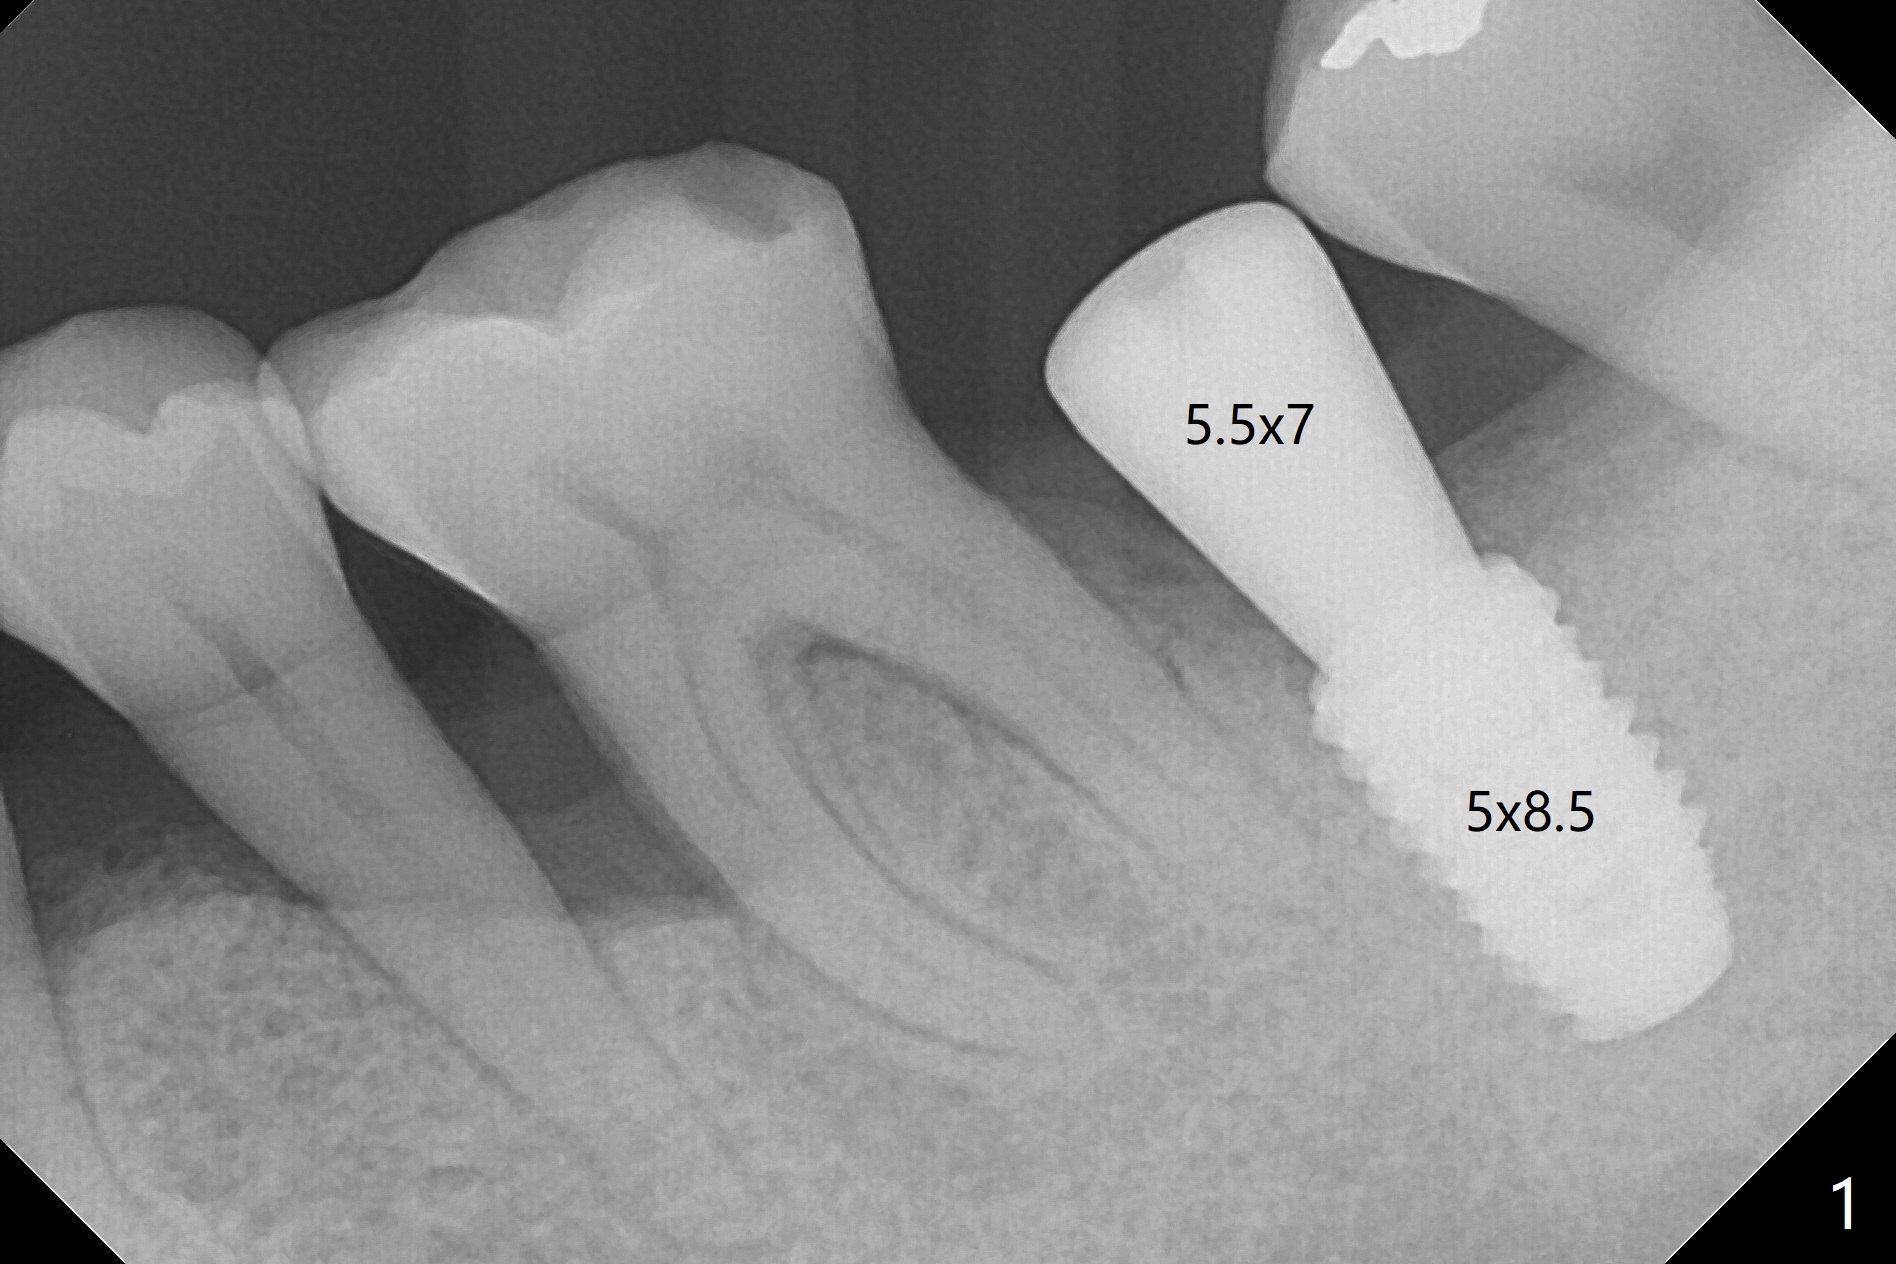

Medium-Sized Implant for Narrow Mesiodistal Space

After a 5x8.5 mm implant is placed at #18, it is difficult to place a 6.5 mm healing abutment, since it prematurely contacts the tooth #17. When the postop PA is taken (Fig.1), the implant appears to be close to the root of the tooth #19. The former may block the blood supply to the distal root of the tooth #19. A 4 mm implant may be sufficient for the narrow mesiodistal space.